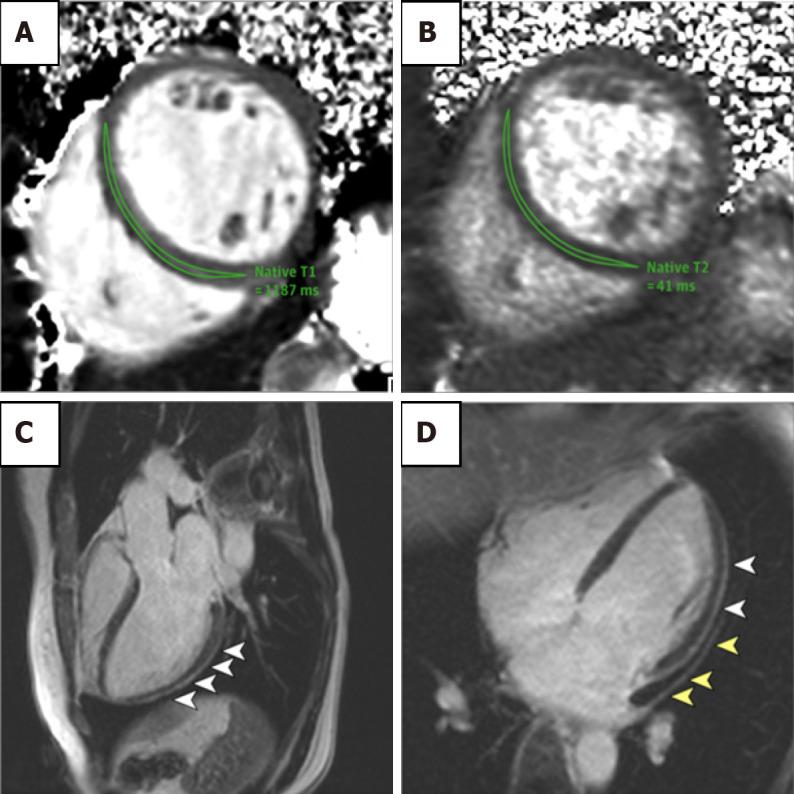

Cardiac magnetic resonance imaging (MRI) is an evolving technology, proving to be a highly accurate tool for quantitative assessment. Most recently, it has been increasingly used in the diagnostic and prognostic evaluation of conditions involving an elevation in troponin or troponinemia. Although an elevation in troponin is a nonspecific marker of myocardial tissue damage, it is a frequently ordered investigation leaving many patients without a specific diagnosis. Fortunately, the advent of newer cardiac MRI protocols can provide additional information. In this review, we discuss several conditions associated with an elevation in troponin such as myocardial infarction, myocarditis, Takotsubo cardiomyopathy, coronavirus disease 2019 related cardiac dysfunction and athlete's heart syndrome.

心脏磁共振成像(MRI)是一项不断发展的技术,已被证明是一种用于定量评估的高度准确的工具。最近,它越来越多地用于涉及肌钙蛋白升高或肌钙蛋白血症的疾病的诊断和预后评估。尽管肌钙蛋白升高是心肌组织损伤的非特异性标志物,但它是一项经常进行的检查,导致许多患者无法得到明确诊断。幸运的是,更新的心脏MRI检查方案的出现可以提供更多信息。在这篇综述中,我们讨论了几种与肌钙蛋白升高相关的疾病,如心肌梗死、心肌炎、Takotsubo心肌病、2019冠状病毒病相关的心功能障碍和运动员心脏综合征。